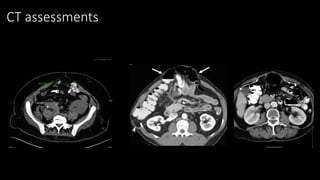

A situation best assessed by CT scan

 Abdominal wall defect

measurement

 Multiplicity

 Domain loss: >30% of

abdominal volume in

hernia

 Previous mesh

position

 Obesity

 Stoma position

CT assessments